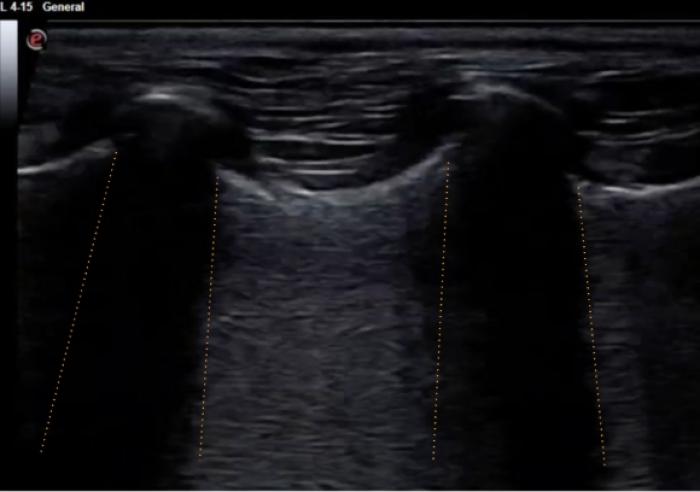

Comenzaremos posicionando el transductor perpendicular a las costillas en uno de los espacios intercostales, pudiendo evaluar al menos el espacio entre dos costillas, la línea PP y no más de 2-3 cm de profundidad de campo (Figura 1A-B).

Son visibles en todo pulmón bien ventilado, pero también estarán presentes en el neumotórax por lo que en este punto es vital observar el deslizamiento de la LP para su diferenciación (Figura 3A-B).